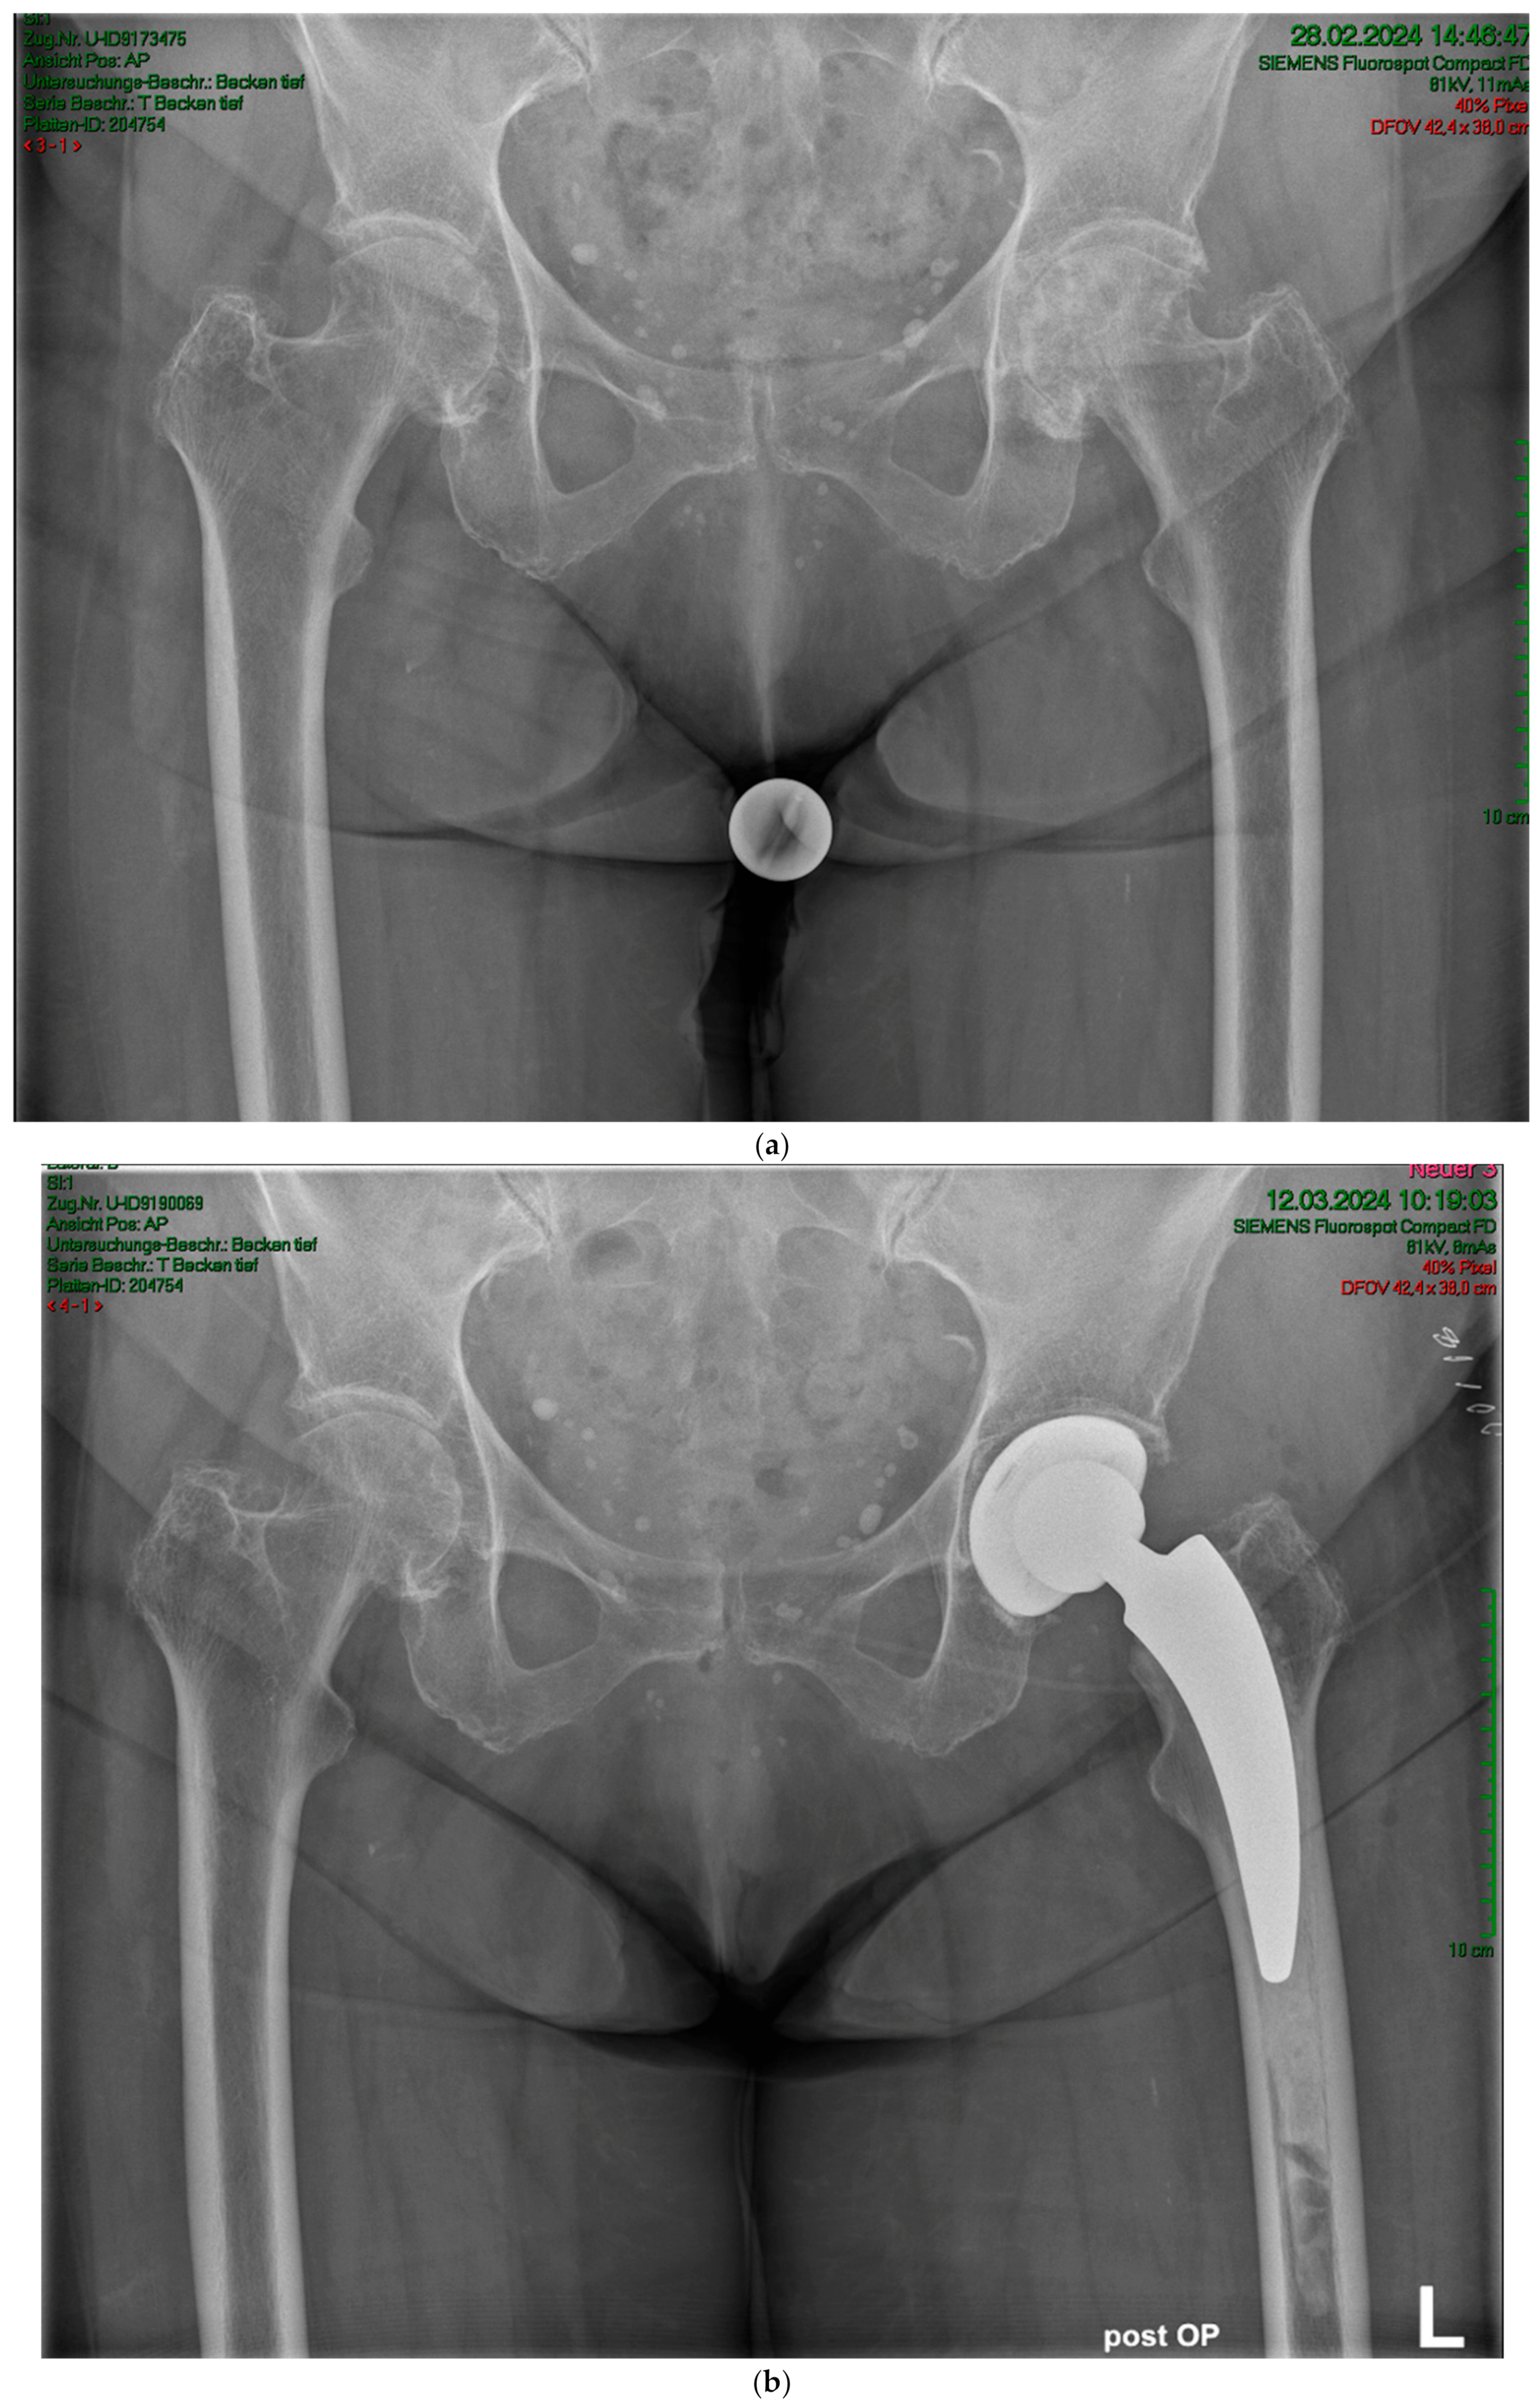

Figure 2.

Case #1: Female patient, 81 years old, with osteoporotic bone, coxa vara, and a Dorr C femur. (a) Preoperative planning for a cemented A2 stem combined with a cementless ANA.NOVA Alpha Cup. The image shows good reconstruction of the leg length and offset. (b,c) Postoperative anteroposterior (b) and axial (c) radiographic imaging 1 week postoperatively. Correct position of the stem and complete cement mantle.